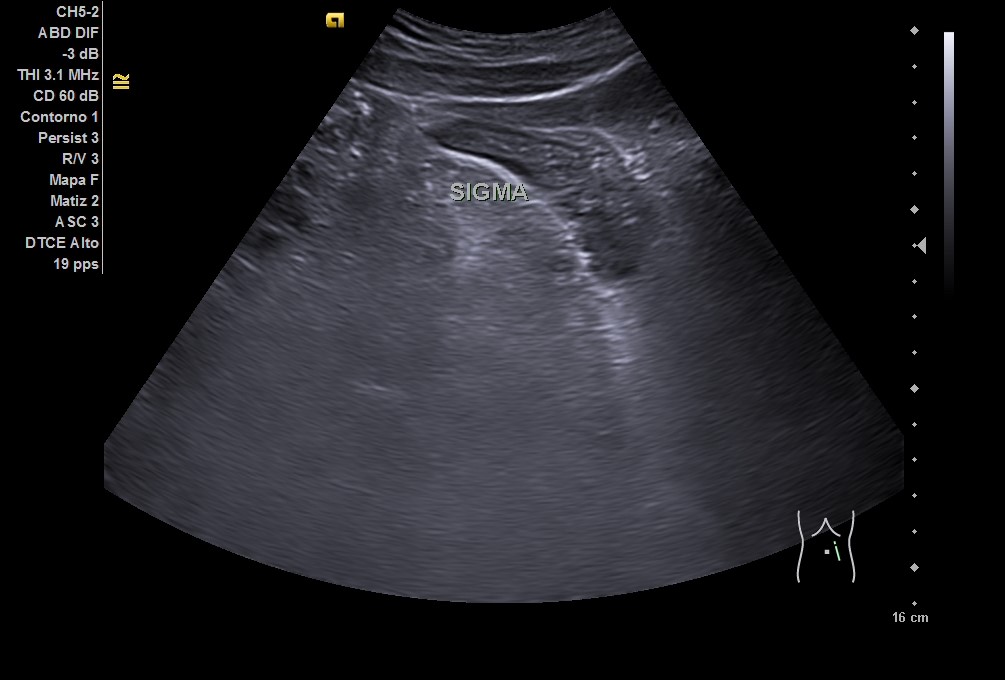

En ecografía clínica: hígado homogéneo sin lesiones, vesícula biliar sin litiasis. Riñones de forma, tamaño y ecoestructura normales. Arteria aorta sin dilataciones. Vejiga levemente repleccionada, ausencia de líquido libre en fondo de Douglas. Asa de sigma con posible edema de pared. Ante la clínica y los hallazgos ecográficos, se remite a urgencias del hospital de referencia.